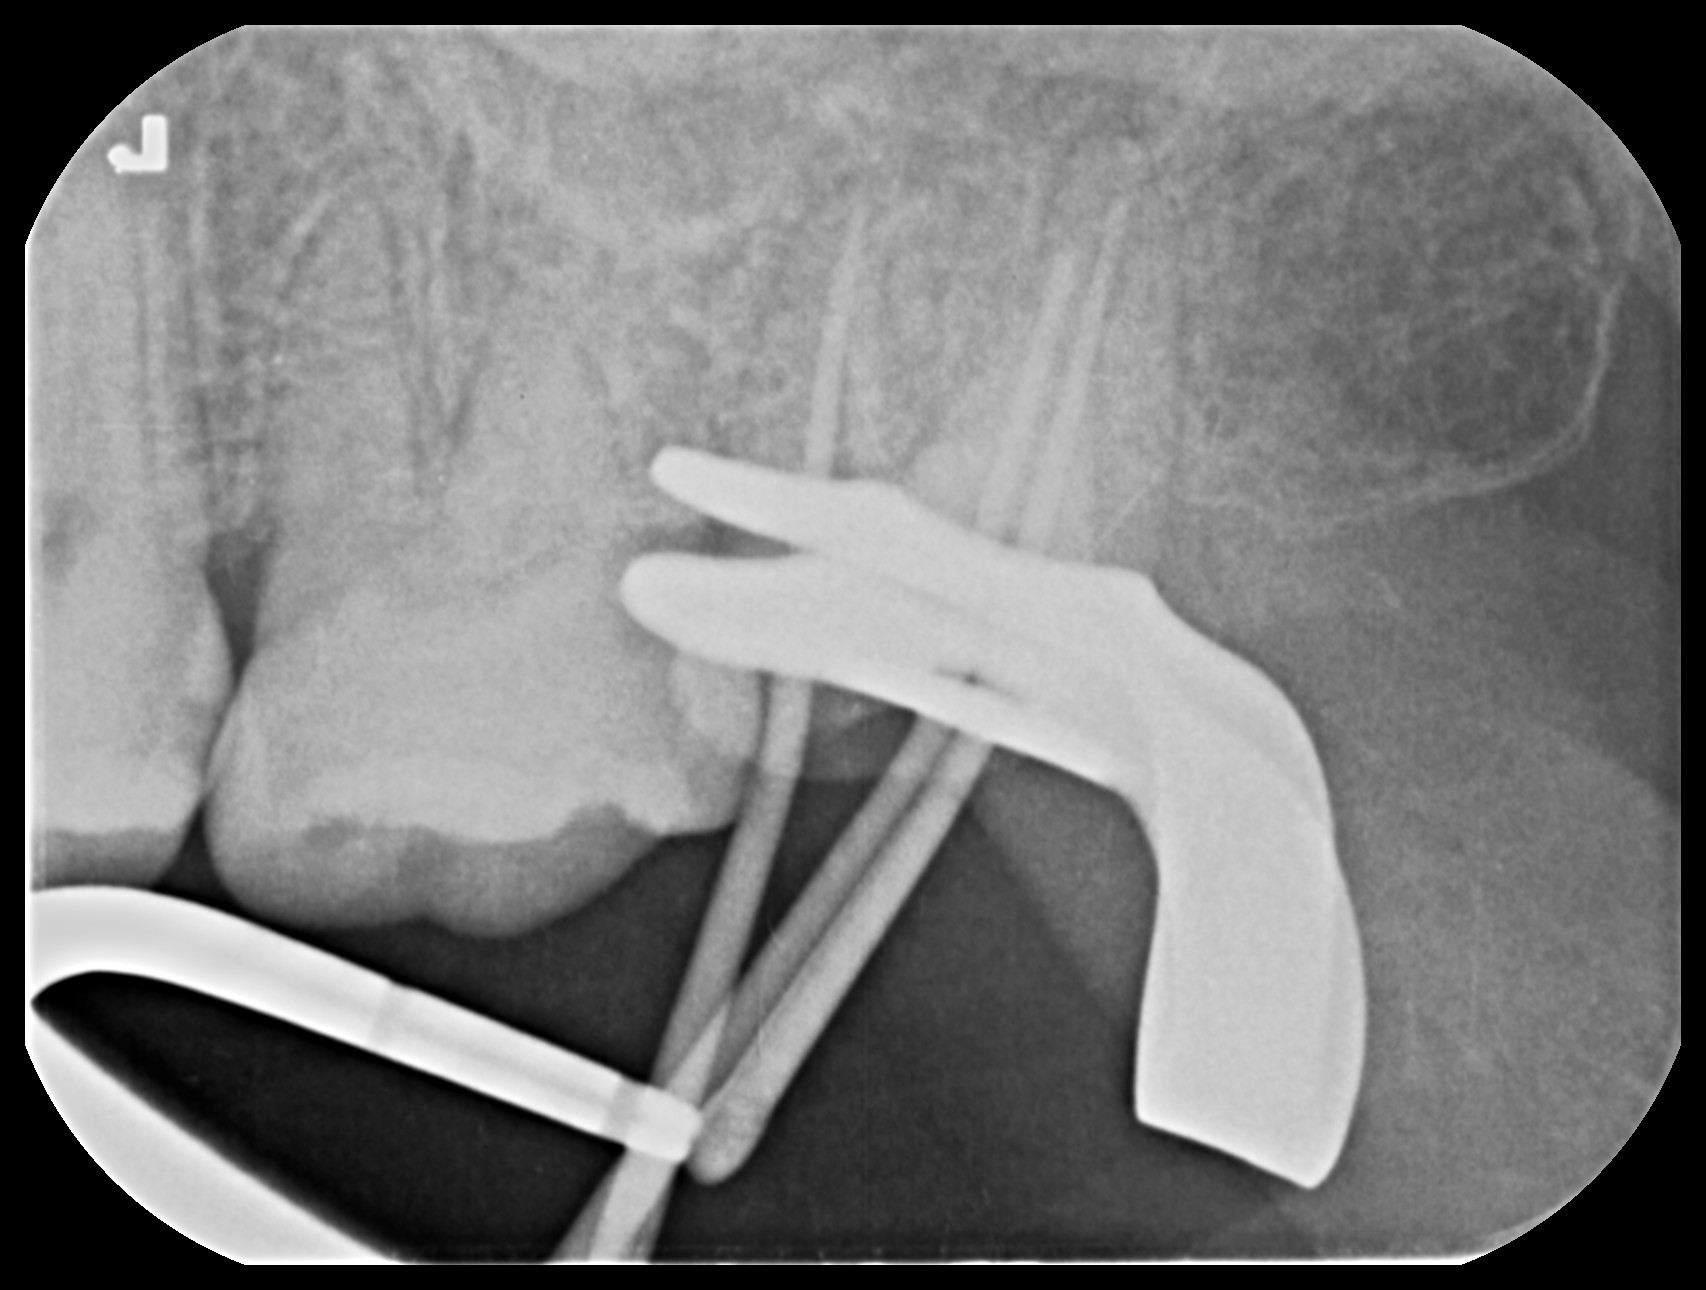

ラバーダム防湿法を行い、治療中に歯の中に唾液や細菌が入ることを防ぎます。

ラバーダム防湿法とは…治療を行う歯のみを露出させ、治療中に唾液や細菌が入ることを防ぎ、再感染のリスクを大きく下げることが可能です。 根管治療は【どれだけ清潔にできるか】が治療成功の鍵となります。 また口腔内に消毒薬が流れ出たり、器具が落下することを防止するメリットもあります。

根尖部までしっかりとお薬を入れることが重要なので、詰める前にレントゲンにて確認をします。 問題なければ、処置を進めていきます。

お薬を詰めた後の写真です。

オレンジ色の部分がお薬を詰めた根管です。

しっかり根尖部までお薬が詰められているか、確認のレントゲンを撮ります。